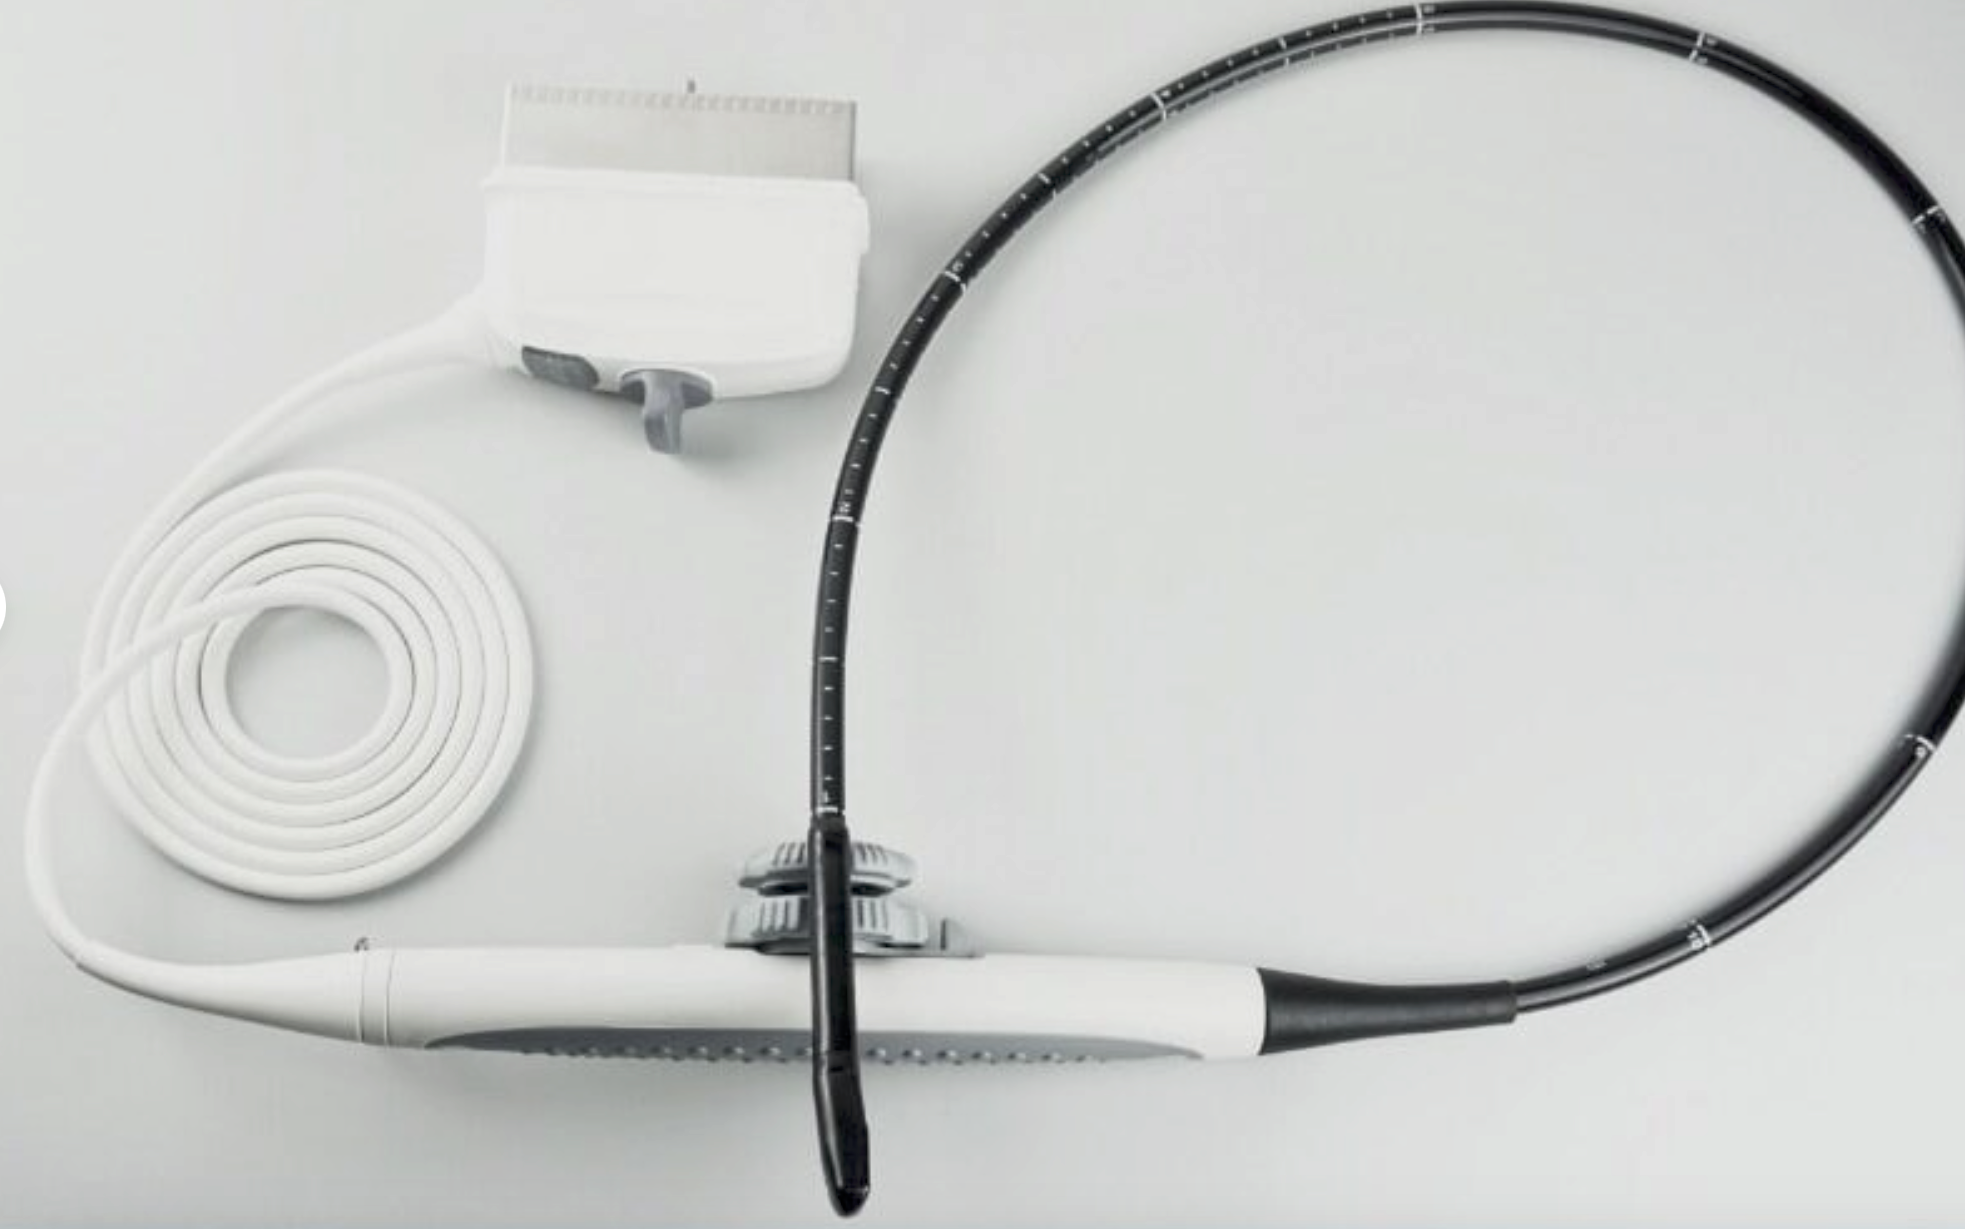

Portable Digital ultrasound scanner laptop machine for human 3.5MHz Convex Probe

The Portable Digital Ultrasound Scanner Laptop Machine for human use comes with a 3.5MHz convex probe. This compact and portable system provides high-quality imaging for various applications, including abdominal and obstetric exams. The laptop design ensures easy mobility, making it ideal for point-of-care diagnostics in clinics, hospitals, or remote settings. With its user-friendly interface and reliable performance, this ultrasound scanner delivers accurate results, enhancing patient care and facilitating efficient medical assessments.